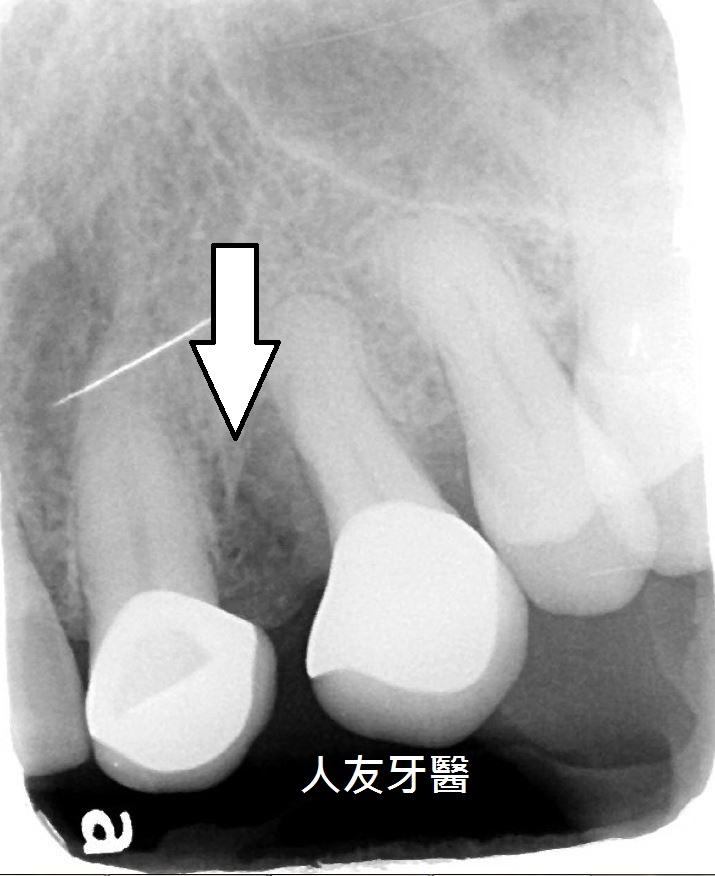

想詢問周醫師如何處理。醫師看了X-RAY發現右邊側門牙紅色圓圈的地方有病變,有可能留不住。左邊側門牙藍色箭頭牙齒有裂到肉,也可能留不住。經過討論後建議都拔除。

拔完牙後一個月,看傷口癒合情況,因兩顆門牙缺牙太久,齒槽骨流失比較多,醫師建議補骨跟植牙同時進行,植入三根牙根,位置分別在於右邊側門牙一顆,右邊正門牙和左邊側門牙。

再用左邊側門牙牙套搭橋到右邊正門牙牙套(三顆相連),右邊側門牙獨立做牙套。使門面變好看,說話也不會漏風。